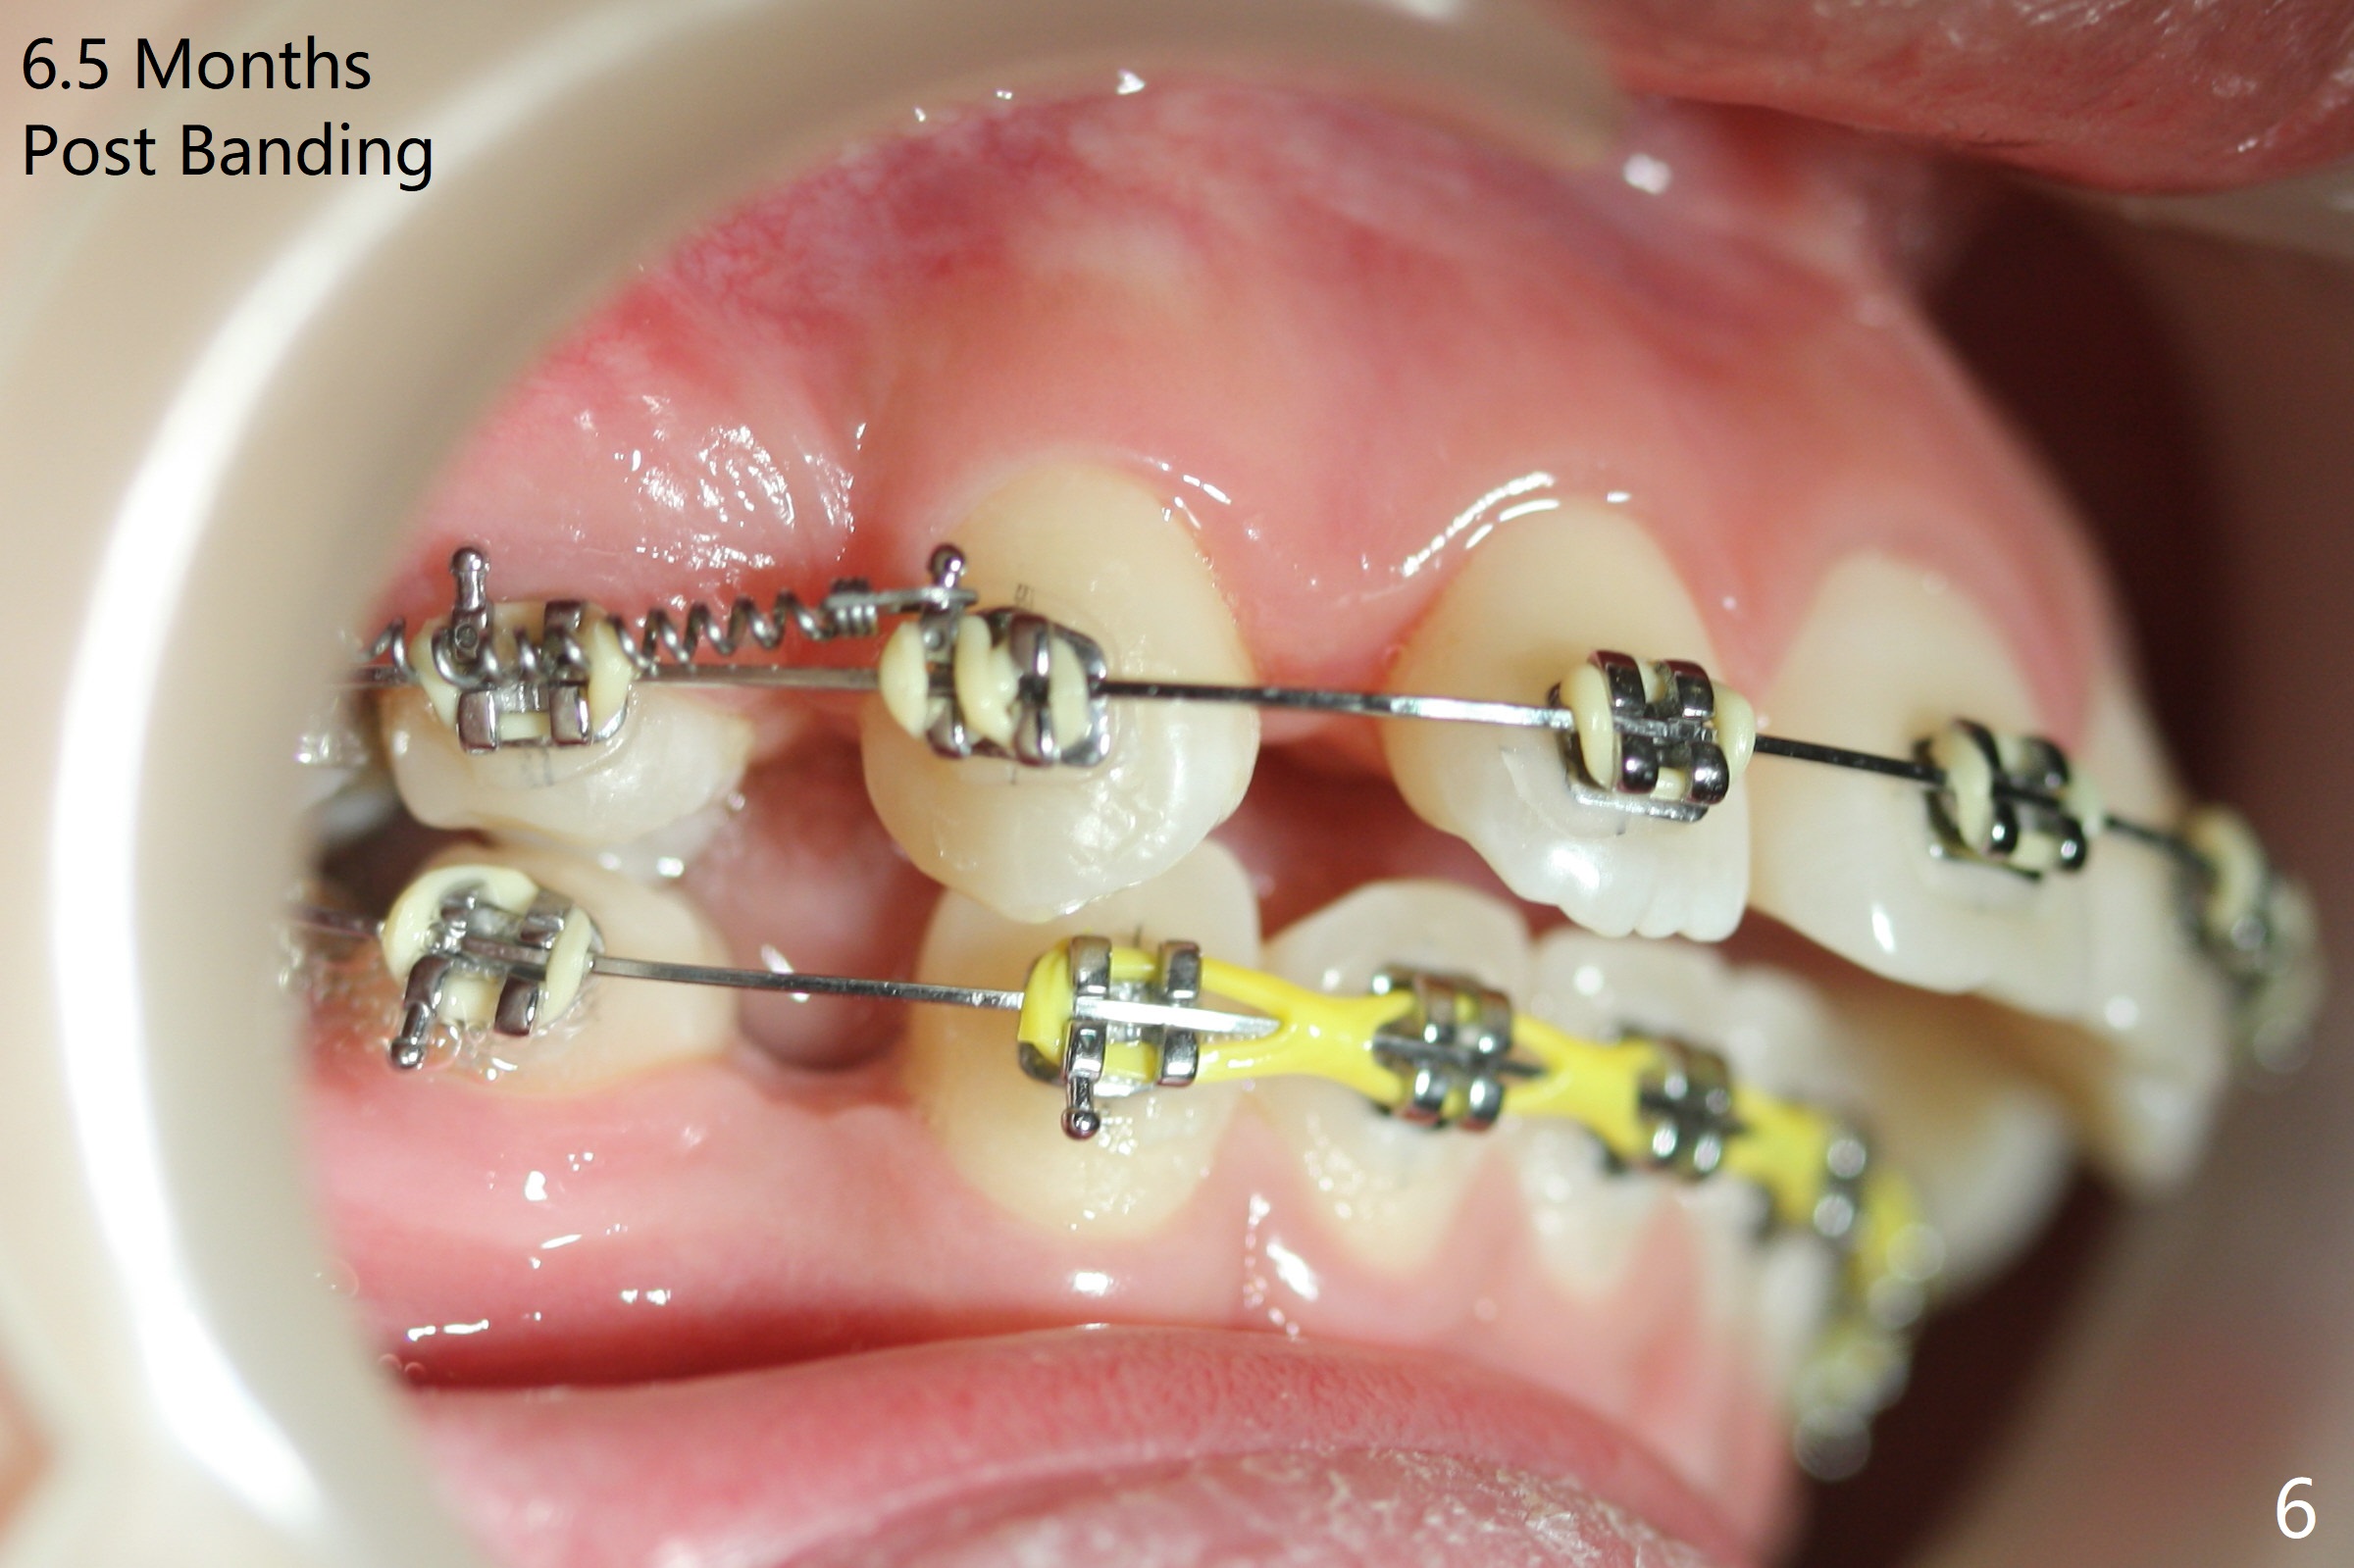

Two weeks post extraction of 4 bicuspids, brackets and bands are placed in 20 teeth (Fig.1-3, 14 niti). No bands are placed at 7s because of short crowns and tight contacts. When 16x16 wires are used, start Class II retraction. The latter is initiated with elastics when 18 ss wires are placed (Fig.4,5). U3s have been distalized with closed springs for 3 months (Fig.6,7). U2s are close to distalization 13 months post banding, 3.5 months post posted wire (Fig,8,9) with overjet (Fig.10). Class II retraction is re-initiated. When the upper incisors are retracted, the anterior overjet remains large. It appears that U6s have been retracted anterior, as indicated by the space between U6/7 (Fig.11), because of no use of U7s as anchors. Brackets are just placed with 18 niti arch wire. They will be retracted distal using the rest of the upper teeth and lower teeth (using Class II retraction) as anchor. There is root resorption of the upper anteriors 2 years 1 month post banding (Fig.12,13).